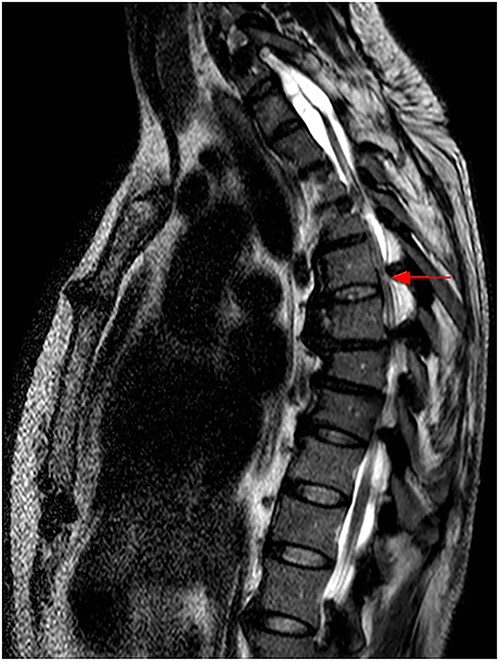

The imaging studies revealed thoracic kyphoscoliosis (with a kyphotic curve of 50°, left upper-thoracic curve of 40° and right lower-thoracic curve of 25°) and significant stenosis of the thoracic part of the spinal canal (particularly at levels Th6, Th9 and Th11) due to severely ankylosed ligamentum flavum (OLF) and the concomitant degeneration of the facets (Figs 1 and 2). Imaging indicated thoracic myelopathy (Fig. 3). We performed emergent posterior wide laminectomy using an ultrasound bone scalpel, and a partial correction of the deformity by instrumented spinal fusion (Th6-Th12). The surgery was performed by the senior author (N.H.).

MRI scan of the thoracic spine at the time of admission, with hyperintense intramedullary T2 signal at Th6, indicating myelopathy (red arrow).